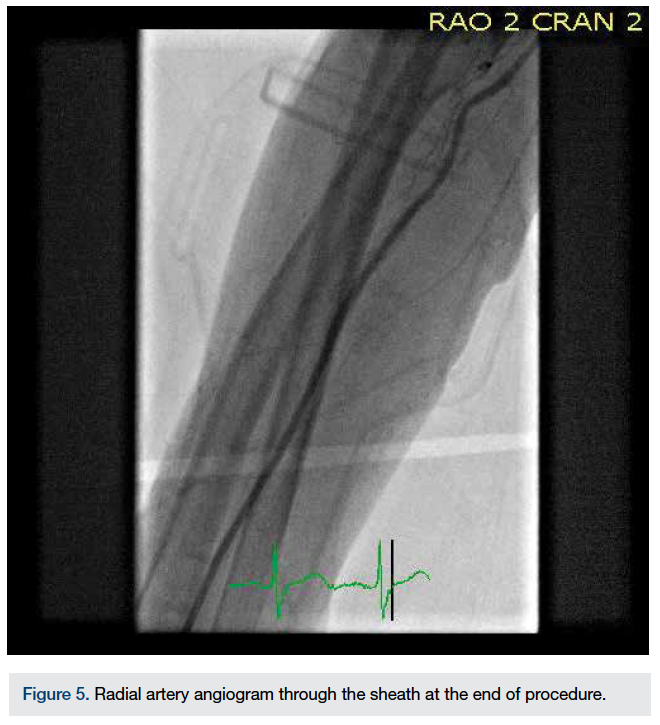

The guide catheter was removed over the J wire and a final angiogram of the RA was performed through the sheath (Figure 5).

There was normal flow in the RA and no dissection was seen. The sheath was removed and a TR Band (Terumo) applied for hemostasis. Patent hemostasis protocol was followed. After 16 hours, at the time of discharge, the RA was patent on a reverse Barbeau test.